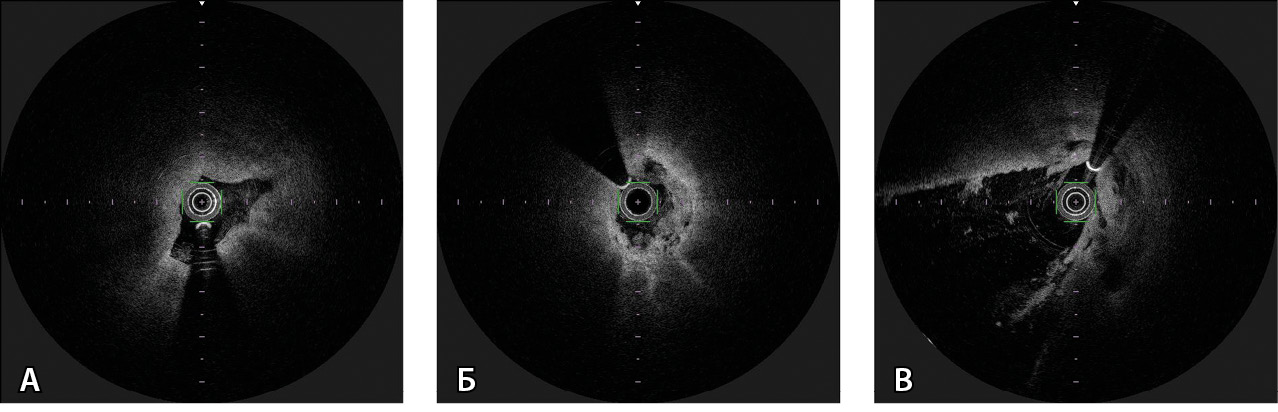

Дальнейшее построение изображения на мониторе ОКТ занимало около 20 секунд. Выполняли оценку и интерпретацию полученных данных, сравнивая с результатами прямой холангиографии. При необходимости автоматическое исследование повторяли. Воспроизводили изображения двух видов: поперечный срез желчного протока из выбранного участка и «комбинированное изображение» продольного среза протока с миллиметровой шкалой для облегчения навигации. Глубина изображения составляла 1–2 мм, что соответствовало визуализации микроструктуры стенки желчного протока с разрешением до 10 мкм. Признаками злокачественного процесса считали выраженное нарушение слоистости структуры и/или наличие множества гипорефлекторных зон неправильной формы (рис. 2).

Рис. 2. Оптическая когерентная томография: поперечные срезы желчного протока в норме и при опухолевых стриктурах. А – неизмененная стенка холедоха. Желчный проток спавшийся, щелевидной формы с четкими стенками и слоями. Б – признаки злокачественной стриктуры: сужение просвета, выраженное нарушение слоистости и наличие множества гипорефлекторных зон неправильной формы. В – гипержелезистая слизистая оболочка холедоха, характерная для опухоли Клацкина